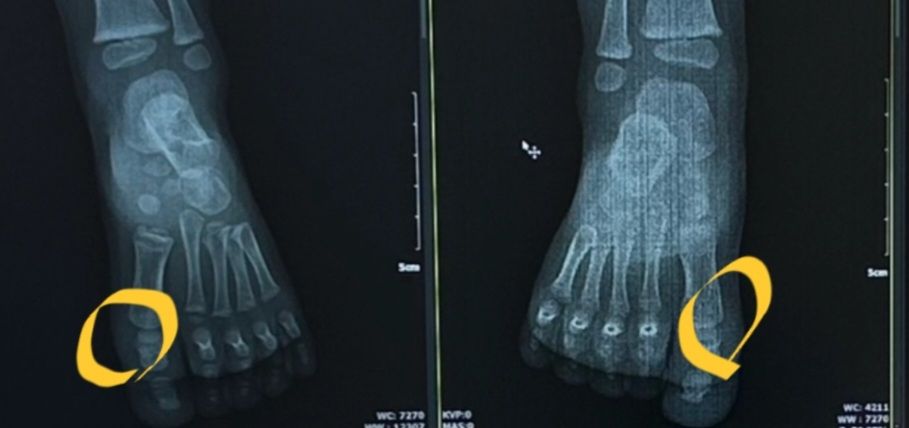

사진에 동그라미부분이 만져지던데

네이버에 발뼈사진 찾아보니 뼈일부인거같더라구요!

엑스레이사진은 다른아기 발뼈사진입니다

• 1번 째 사진

• 2번 째 사진

• 3번 째 사진

• 사진에 동그라미친 부위는 첫번째 발가락의 distal phalanx, proximal phalanx 라고 하는 뼈가 위치한 부위입니다.

당연히 뼈가 잘 만져지는 부위입니다.

피부 바로 아래에 뼈가 있는 부위이기 때문입니다.

• 사진에서 동그라미 친 부분에 뼈가 만져진다는 것은 흔히 보이는 현상입니다.

사진에서 보이는 부위는 아마도 두 번째 발가락의 근위지골(가까운 뼈) 부분일 가능성이 높습니다. 아기의 발은 성장하면서 더 많은 지방과 근육을 얻게 되고, 뼈도 점점 강해지면서 덜 두드러지게 됩니다. 이것은 정상적인 발달 과정의 일부로, 대체로 건강한 징후입니다.

해당부위는 첫 마디뼈 (기절골)에 해당하는 부위로 소아 및 성인에게서 정상적으로 나타나는 부위입니다. 건강상으로는 문제가 없는 상태입니다.

뼈도 몸 어디서든 만져질 수 있고, 말씀하신 부분은 뼈와 뼈가 만나 관절을 이루는 부분이라 더욱 도드라지게 느끼실 수 있습니다. 정상적인 구조물입니다.